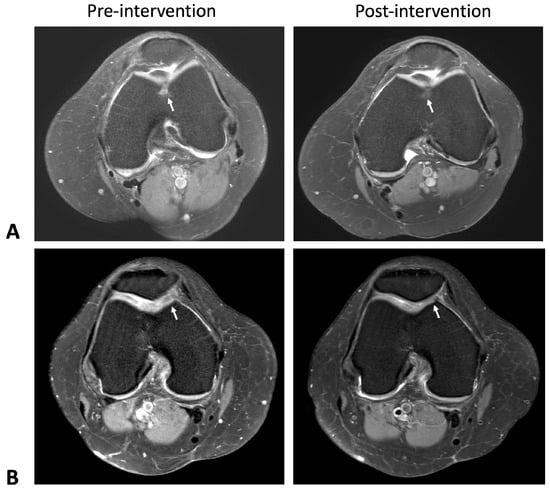

2.1. Cartilage Regeneration and Structural Changes

2.2. Reduction in Synovial Thickness